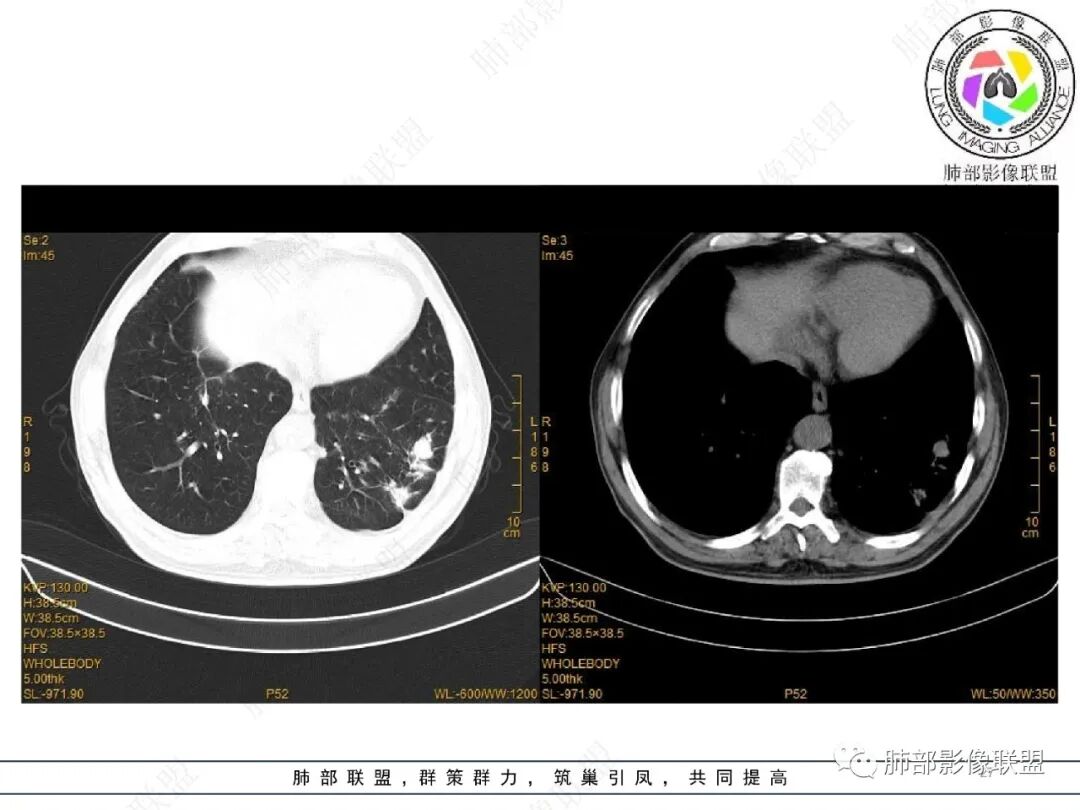

65岁男性。2022.2.17因声音嘶哑入院检查发现肺部病变,未规范治疗出院。2022.4.10因胃出血急诊入院,病情稳定后有咳嗽转入呼吸科治疗,无咳痰、无发热、无呼吸困难。白细胞、中性粒细胞轻度升高,血沉升高,抗髓过氧化物酶抗体IgG阳性,余实验室检查(-)。

2、影像特点:

2022.2.17CT显示两肺中内带多发结节影、斑片影、条索影,部分病灶侧向融合与胸膜平行。部分病灶沿着支气管血管束分布、其内支气管稍扩张。部分病灶呈反晕征。大部分病灶边界显示清晰,部分病灶周围可见边界不清的GGO。2022.4.12CT显示两肺中内带多发结节影、条索状、条带状高密度影,边界收缩平直凹陷,大部分病灶沿着支气管血管束分布,亦有位于胸膜下侧向融合与胸膜平行的病灶。总体与第一次CT对比两肺病灶明显吸收。